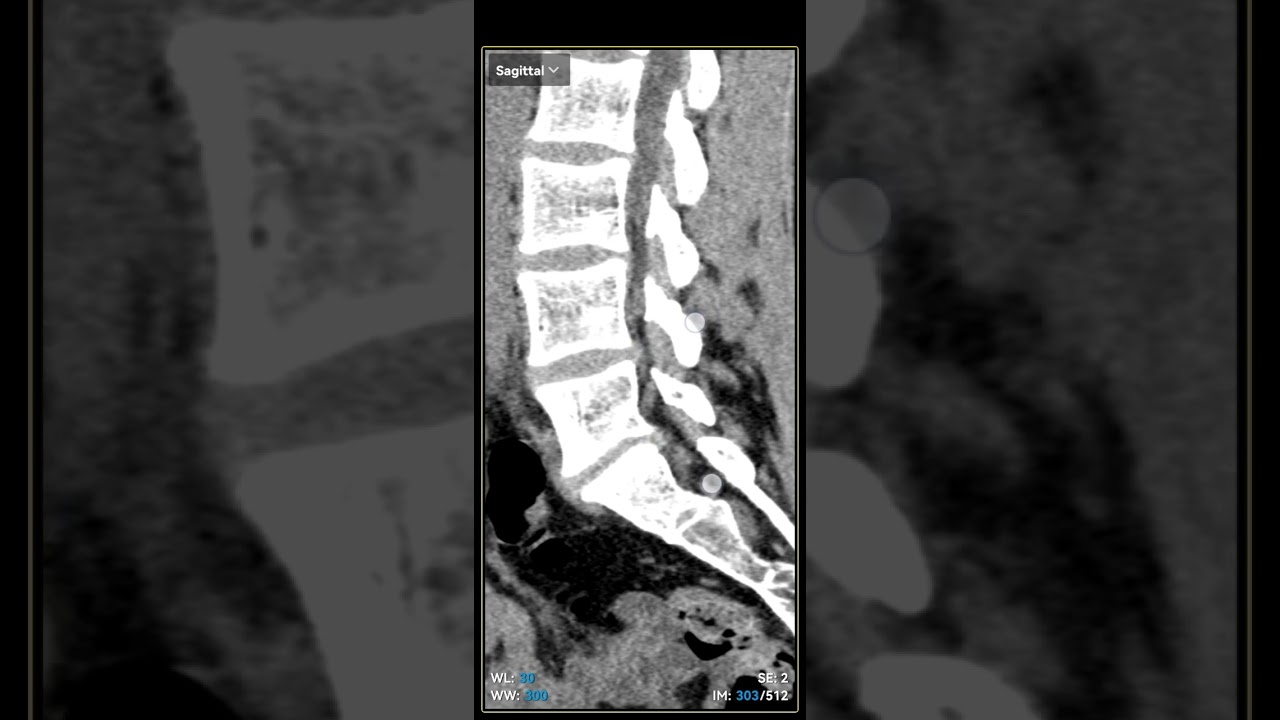

Что покажет компьютерная томография при грыже

- КТ полезна в случае, если МРТ отсутствует или не может быть проведена

- КТ может демонстрировать сужение спинномозгового канала, вызванное спондилофитами

- Грыжевое выпячивание диска визуализируется как экстрадуральное объемное образование в передней части спинномозгового канала, имеющее плотность, эквивалентную мягким тканям (70 Н), и имеет контакт с межпозвонковым диском в межпозвонковом пространстве

- Сагиттальная реконструкция может оказать помощь в определении поврежденного сегмента.